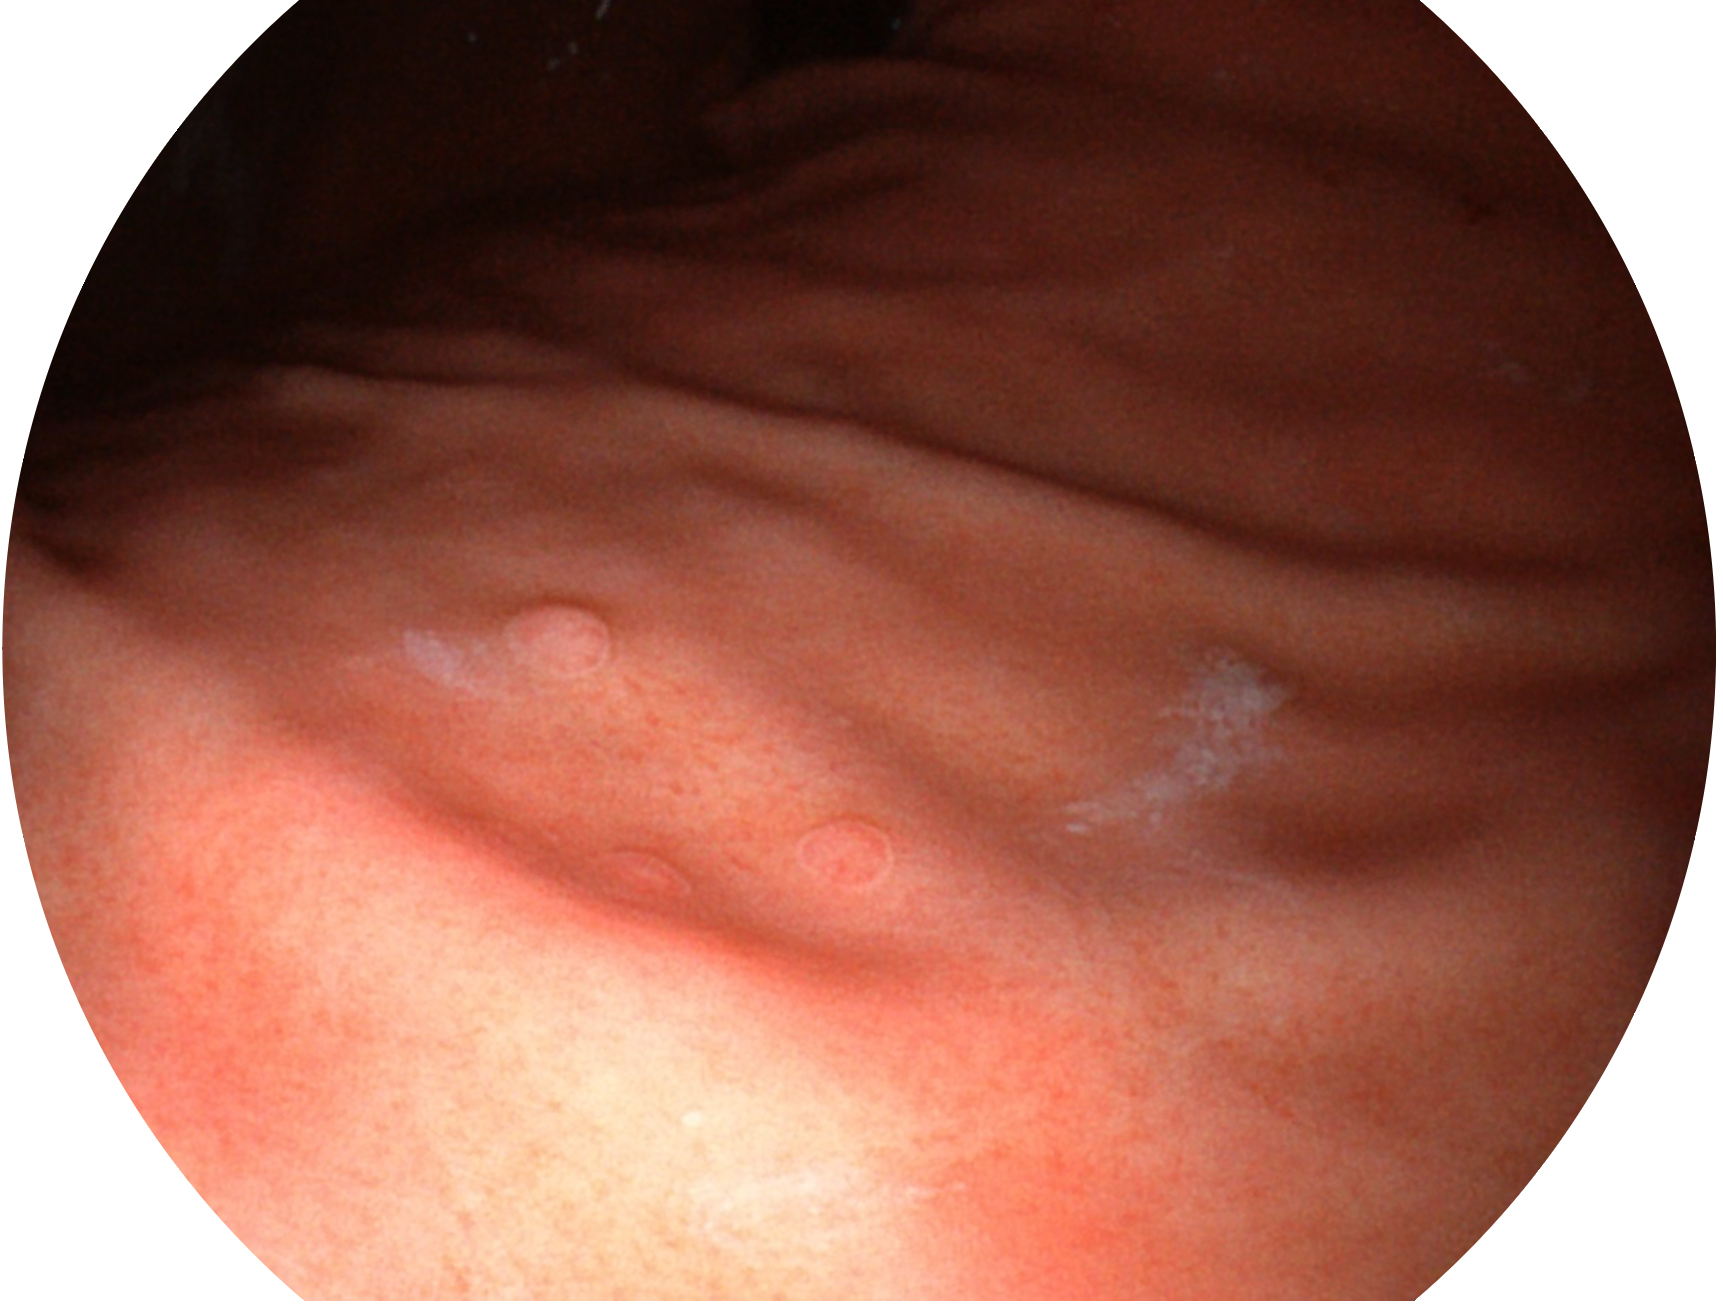

db真人体育官网新开发的内镜染色技术,主要是基于多波长LED 光源的开发,VLS-55Q 四波长LED 光源是由四个不同颜色的LED光按照相应照明模式所规定的特定发光比例进行合束后形成,合束后形成的照明光的光谱由红光、绿光、蓝光及蓝紫光这四个不同的波段范围构成。具有更高光谱自由度,通过光谱比例的控制,实现了聚谱成像技术,英文全称为“Spectral Focused Imaging, SFI”,缩写为“SFI”和光电复合染色成像技术,英文全称为“Versatile Intelligent Staining Technology, VIST”,缩写为“VIST”。